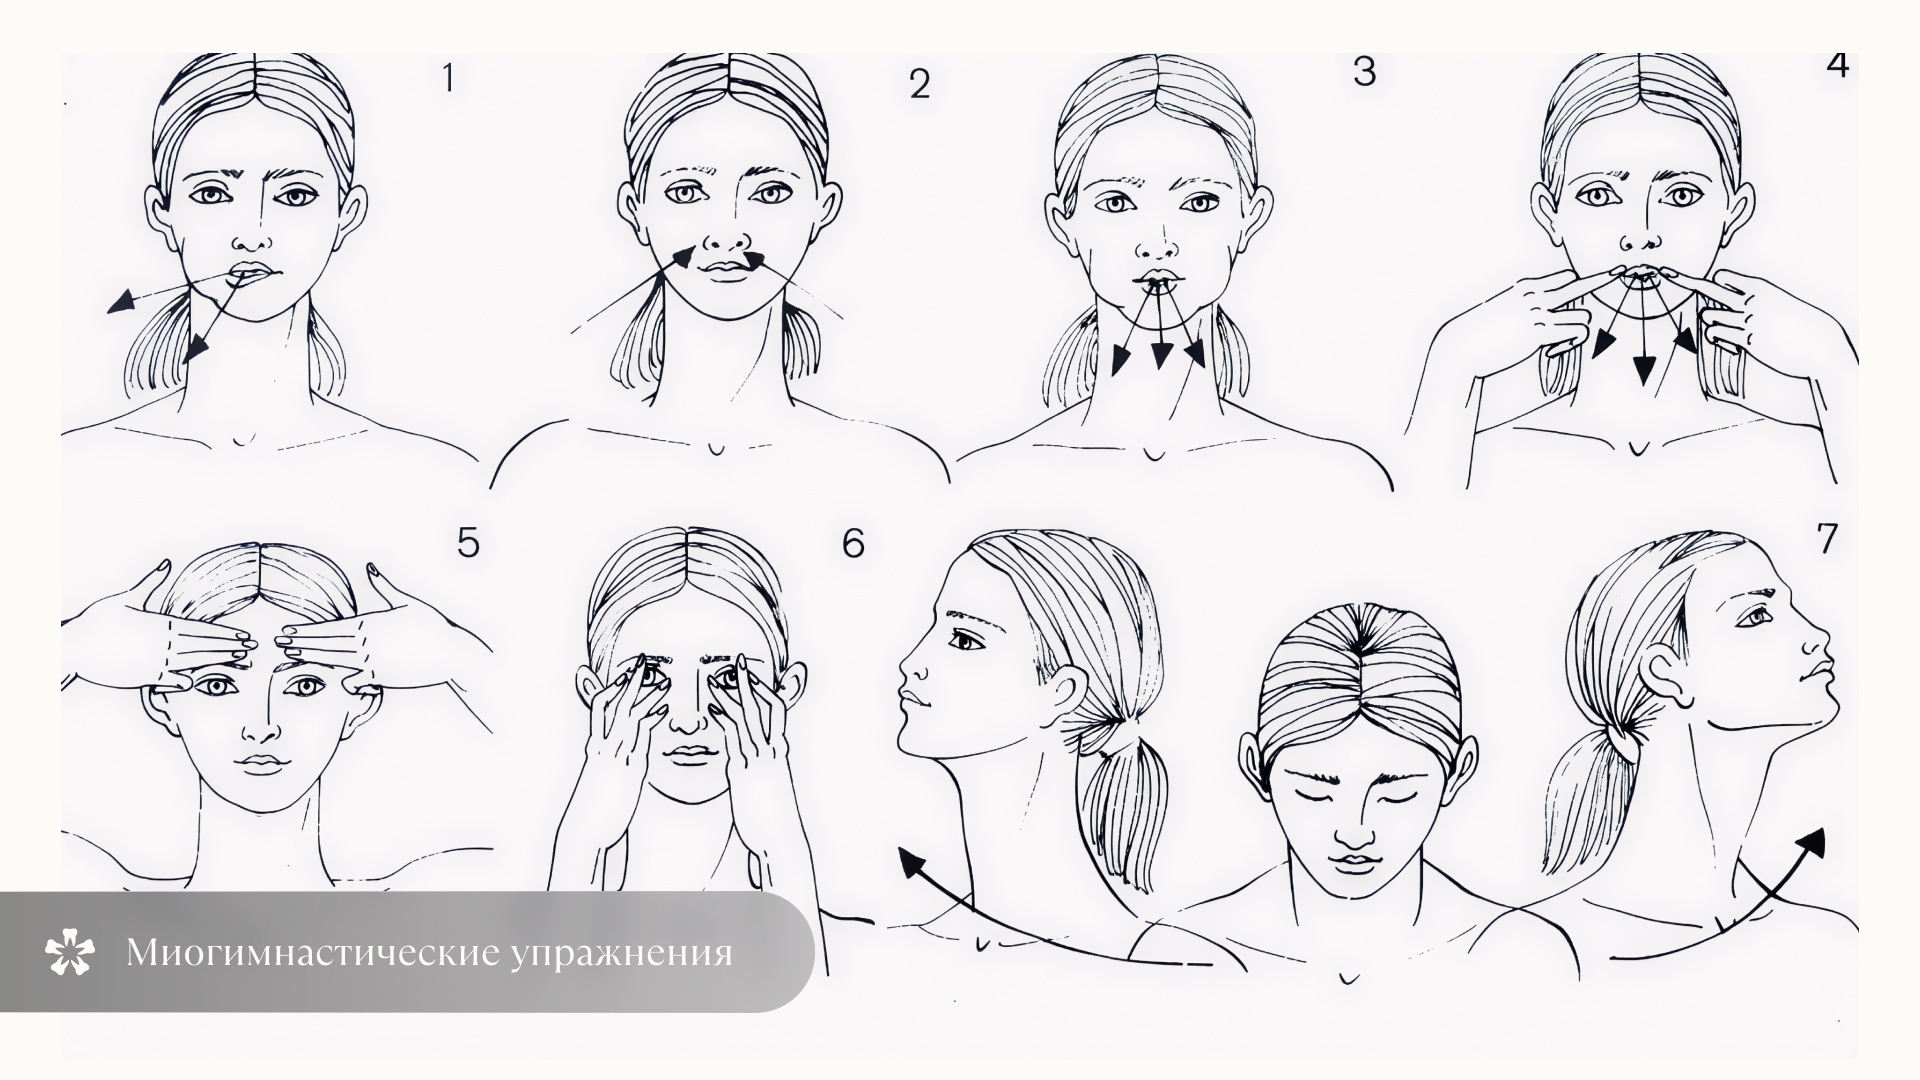

Механизм: силиконовые каппы, которые выравнивают зубы, нормализуют тонус мышц, обучают правильному положению языка, формируют правильную окклюзию.

Возраст: от 4 до 10 лет — в период активного роста челюстей.

Плюсы: мягкое воздействие, съемный аппарат, подходит для ранней коррекции. Особенно эффективен в сочетании с логопедией, миогимнастикой.

Минусы: не подходит при сложных , комбинированных формах патологии. Требует регулярного ношения и дисциплины, а также необходимо наличие свободного носового дыхания у ребёнка.

Механизм: формирует правильные речевые привычки, положение языка при глотании и разговоре. Устраняет прокладывание языка, которое мешает смыканию зубов.

Возраст: с 3 лет и старше, по показаниям.

Плюсы: помогает закрепить результаты ортодонтического лечения, обязательна при функциональной природе окклюзии.

Минусы: требует времени, регулярных занятий и вовлеченности родителей.

Механизм: устранение внешнего давления на челюсть и зубы: сосание пальца, пустышки, прикусывание предметов, сон с запрокидыванием головы. Часто назначаются миогимнастика, вестибулярные пластинки., Возраст: чем раньше — тем лучше. Оптимально до 4–5 лет.

Плюсы: позволяет избежать развития неправильной окклюзии или стабилизировать легкие формы без аппаратного лечения.

Минусы: психологиче�ски сложный этап, требует терпения, особенно при стойких привычках. Необходима кооперация пациента и родителей.